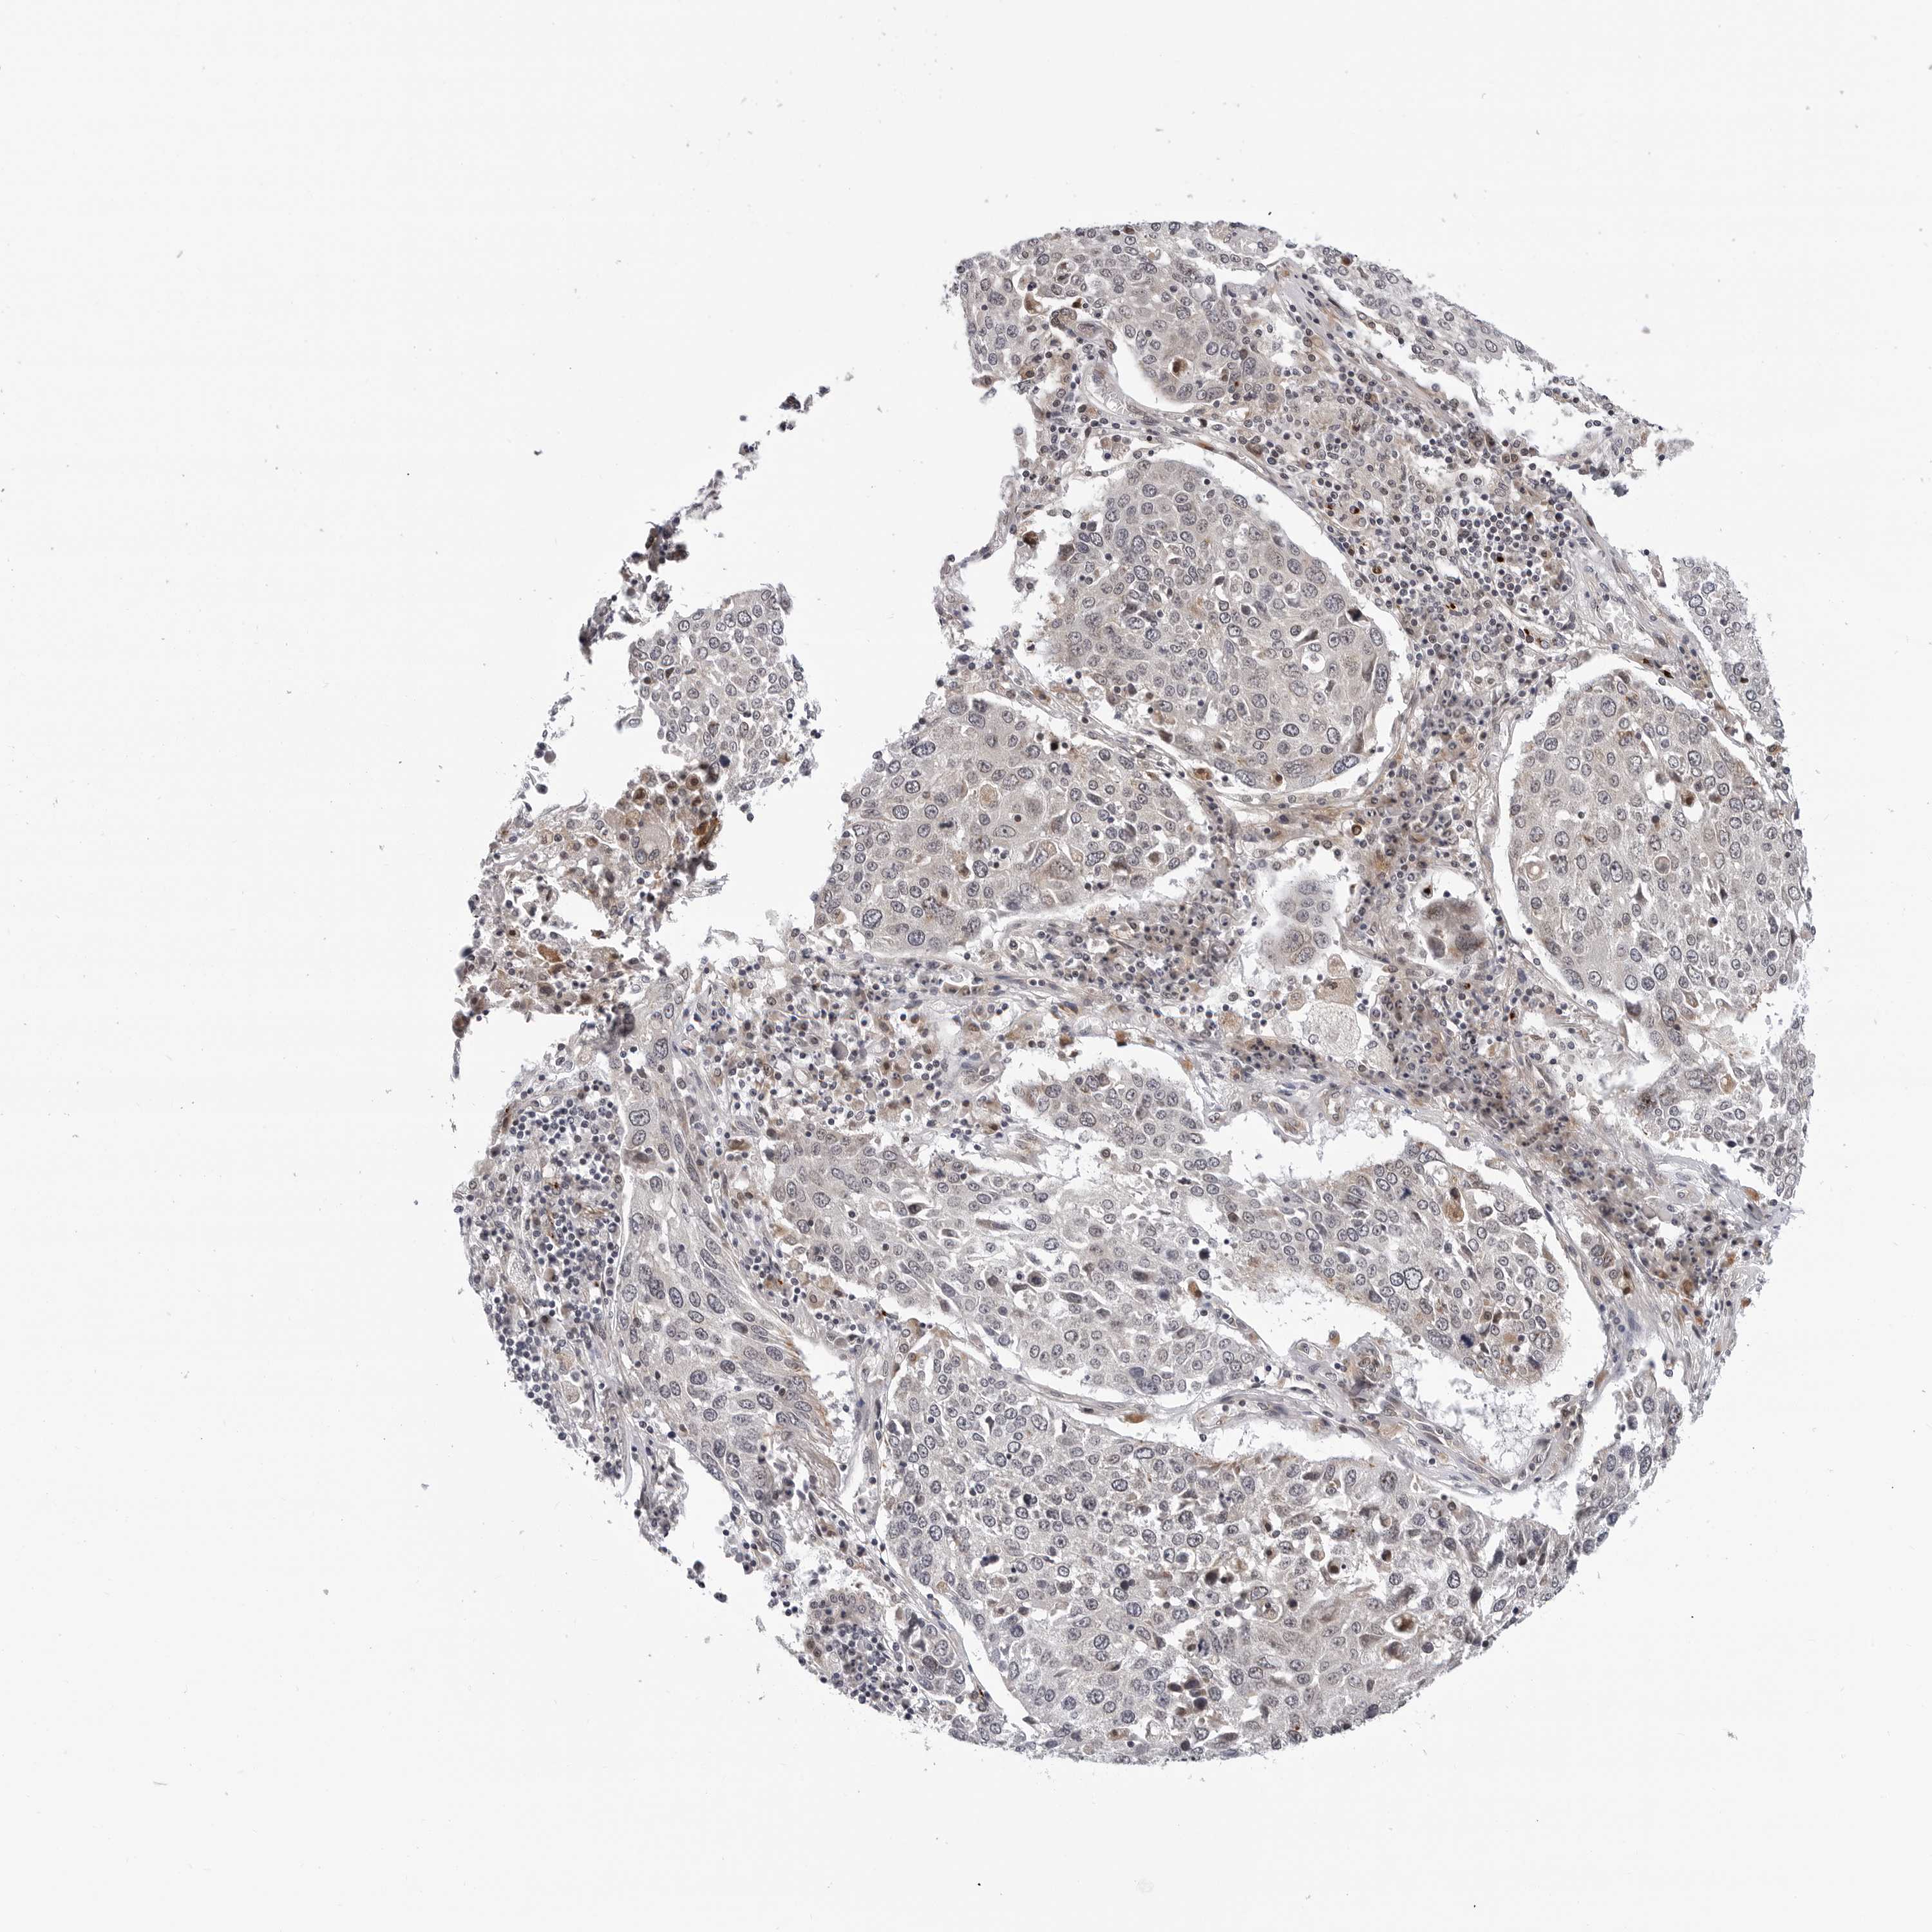

CANCER LUNG CANCER Show tissue menu

Lung cancer

Human cancer

Lung adenocarcinoma

Lung squamous cell carcinoma